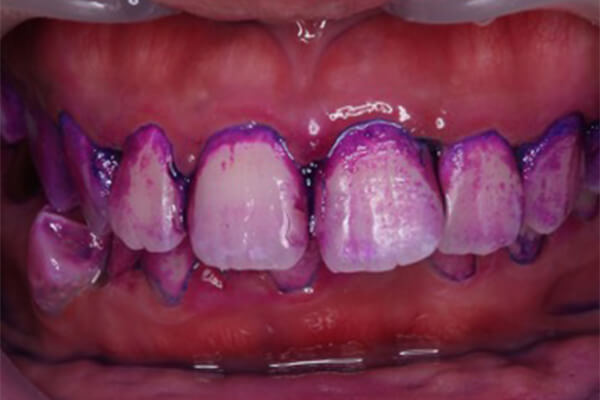

治療前

治療後

プラークは炎症の初発因子となります。ここから歯肉の炎症が始まり、歯周病や虫歯の進行につながります。

写真はプラークを染め出す液体を歯の表面に塗布してゆすいだ前後のものです。一見だいぶ綺麗に磨けているように見えますが、歯と歯茎の境目などは色濃く目立っており、磨き残しが多いことがわかります。プラークは粘着性が強く、放置することでさらに細菌の停滞をしやすい状況を作ります。プラークコントロールはそれを防ぐための手段となります。